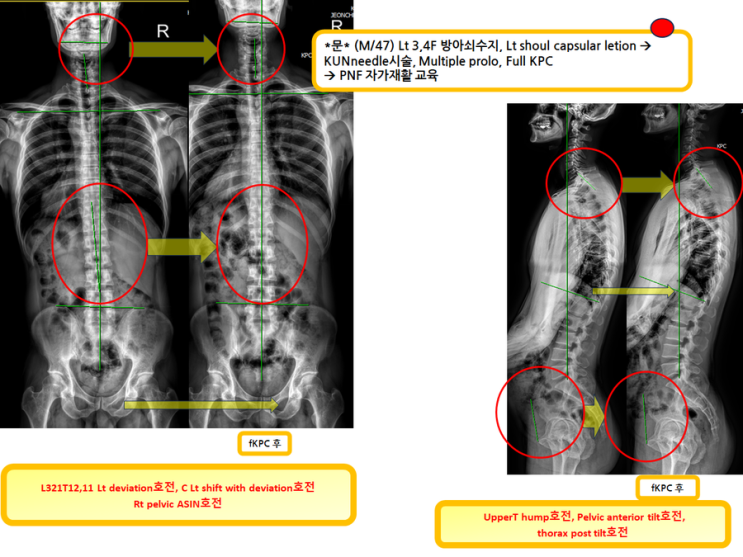

무릎외측통증이 주소인 환자분!(녹는실KPC치료는 엑스레이 호전을 10분만에 확인)

무릎외측통증이 주소인 환자분! (녹는실KPC치료는 엑스레이 호전을 10분만에 확인) 전에 했던 장경인대 ...